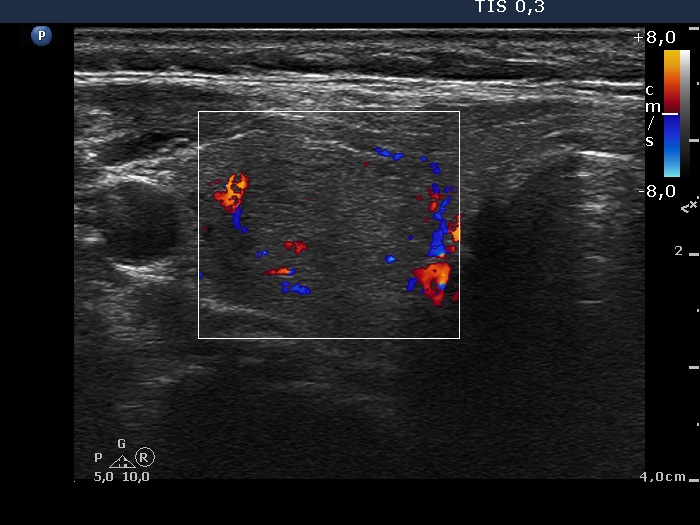

Study on 100 consecutive patients with thyroid nodule - case 066 (ultrasonographic picture 7)

Lowest part of the right lobe, transverse scan, color Doppler mode. This nodule presents perinodular blood flow.